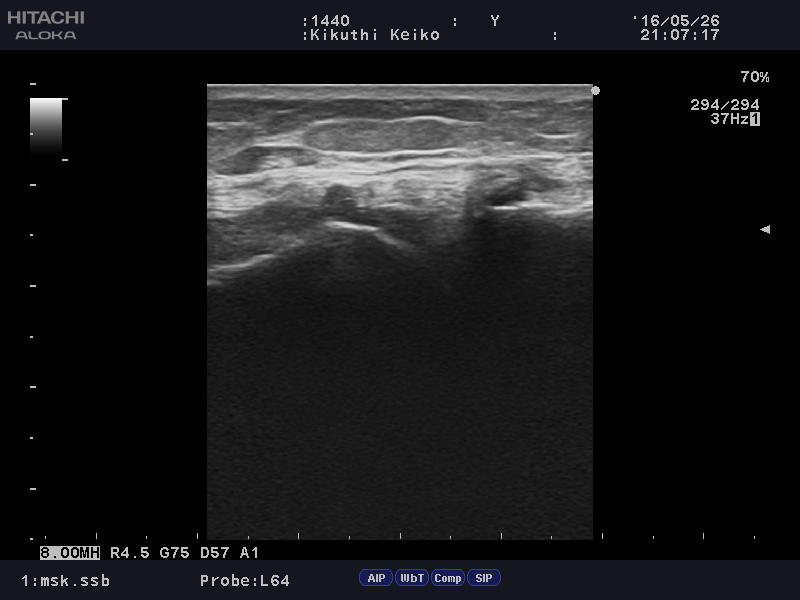

階段を下っている時に足を踏み外し「膝の靭帯」を痛められた方。

Medial collateral ligament2.JPG